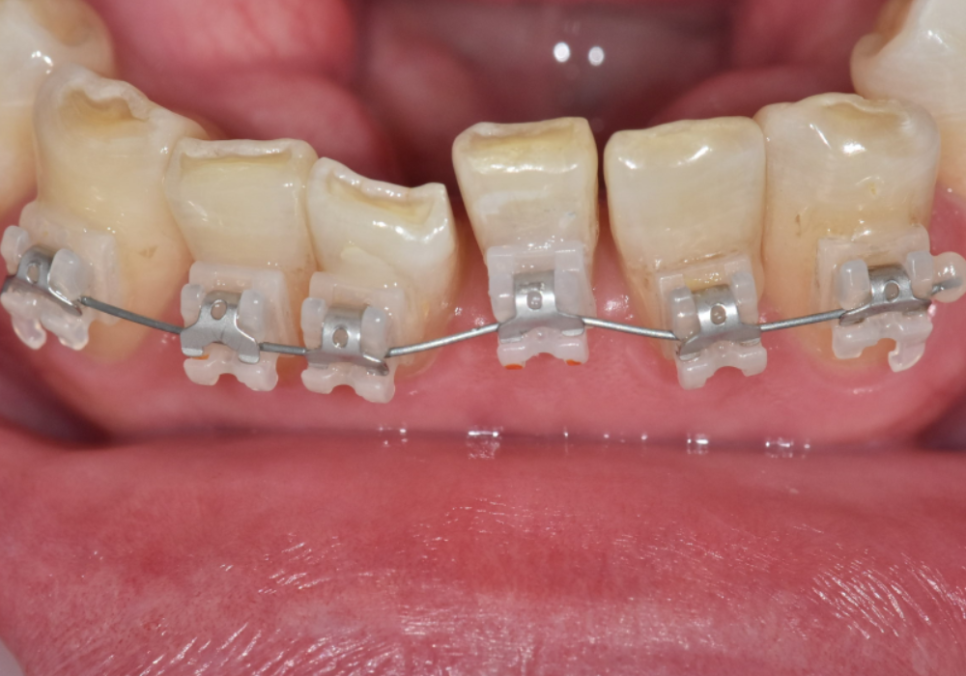

똑똑한 '똑딱이' 클리피씨

명일역 앞니 부분 교정

사회생활을 활발히 하시는 젊은 분들은

교정을 고민할 때 '심미성'과 '효율성'을

가장 중요하게 생각하시죠.

이번 환자분도 소위 '철길'이라 불리는

금속 브라켓은 큰 부담이라 하셔서,

저희는 '클리피씨(Clippy-C)'라는

자가 결찰 브라켓을 선택했습니다.

250328

하지만 클리피씨는 장치 자체에

슬라이딩 캡(뚜껑)이 달려 있습니다.

클리피씨 방식 (뚜껑 열고 닫는 방식으로 간편해짐)

클리피씨도 와이어를 넣고 뚜껑만 닫으면

고정이 끝나는 방식이라 훨씬 간결합니다.

그러다 보니, 진료시간이 짧고

마찰이나 통증이 적어요.

게다가 치아 색과 비슷한 세라믹 재질이라

금속 장치보다 훨씬 자연스러워서,

크게 티가 나지 않는다는 게 큰 장점입니다.